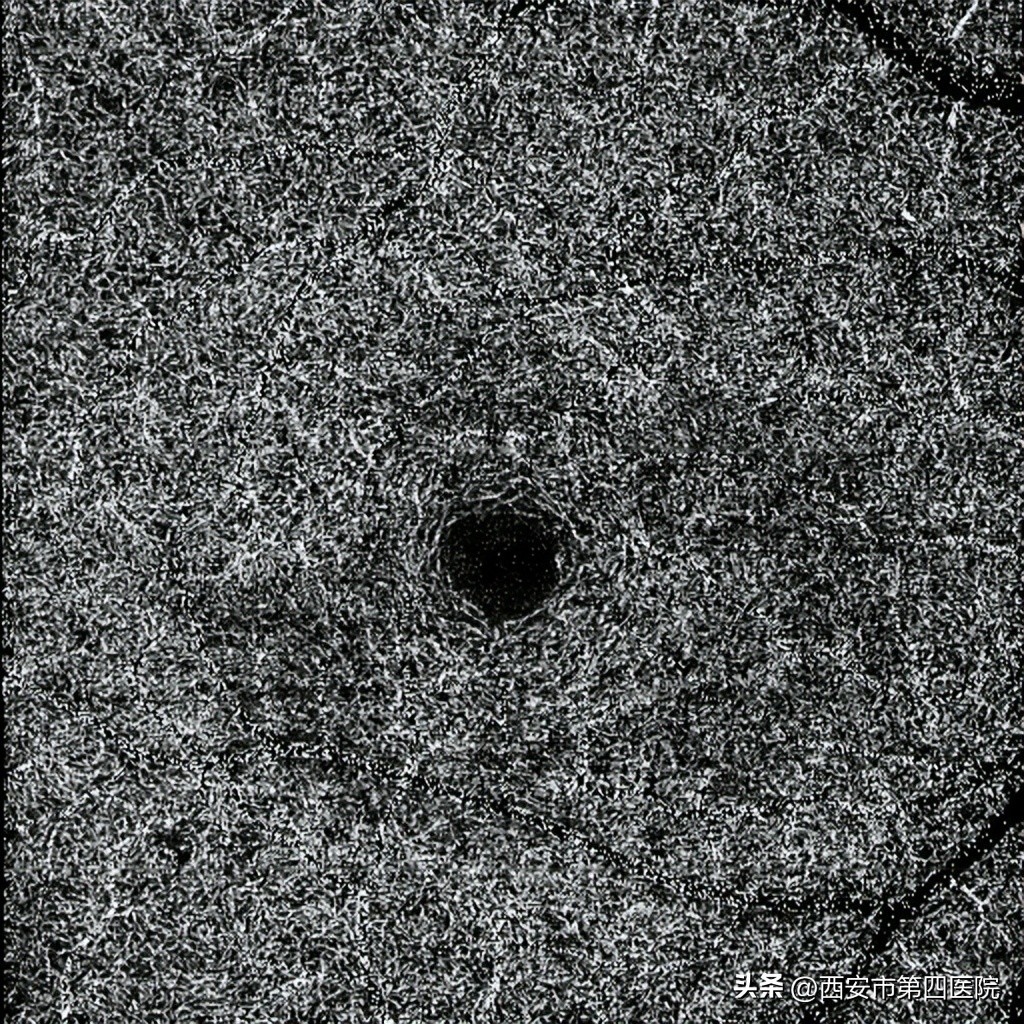

双眼OCTA6*6mm检查: 黄斑周围深层毛细血管血流密度降低。

OCTA显示视网膜深层毛细血管网血流密度降低。